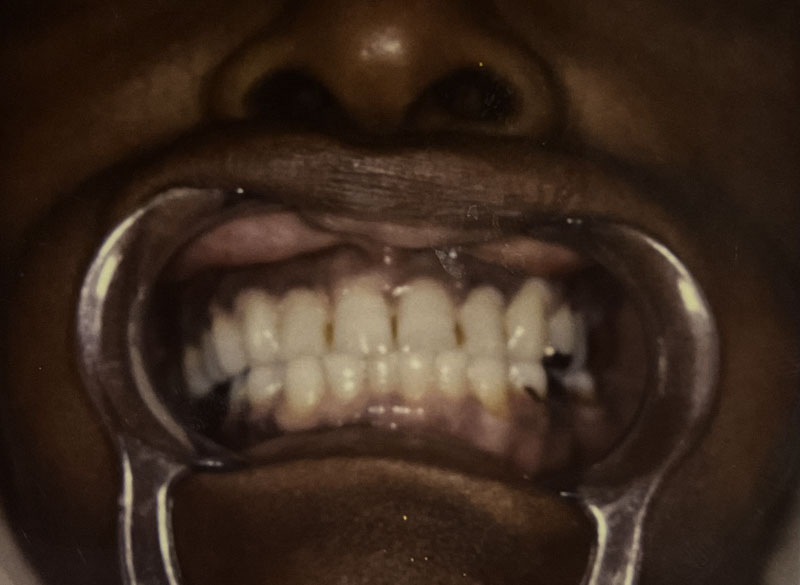

Custom Cosmetic Crowns

Case Highlight

Before

After